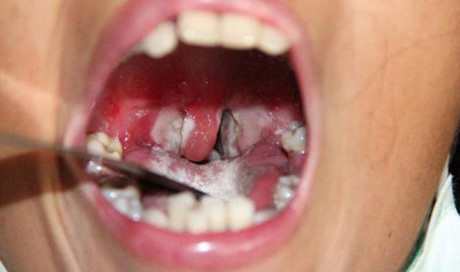

| Lớp màng trắng trong cổ họng người bệnh bạch hầu - Ảnh minh họa |

- Xuất hiện một màng dày trắng ngà bao phủ cổ họng, amidan, thanh quản, mũi, lưỡi… Đây cũng chính là dấu hiệu điển hình của bệnh bạch hầu.

- Lớp màng trắng trong cổ họng người bệnh bạch hầu